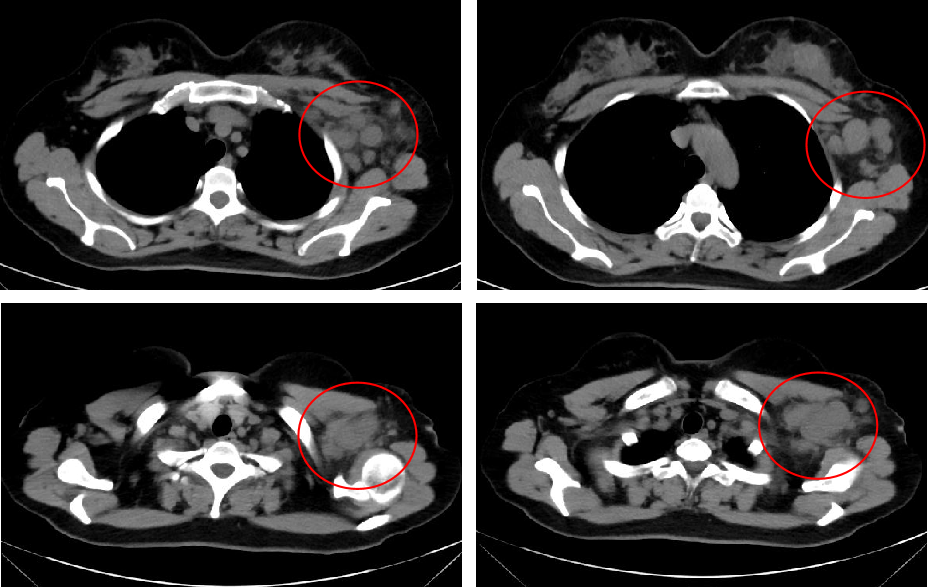

放疗:患者病理缓解未达理想状态,术后行局部放疗,同时申请入组“新辅助治疗后存在浸润癌残留的HER2阳性乳腺癌辅助治疗研究”。放疗期间进行临床研究入组筛选时,发现患者存在脑转移,肿瘤负荷大。

图片4.png

疗效评估:颅内病灶迅速缩小,总疗效评价为PR,大部分病灶呈影像学完全缓解状态(CR)。

• MRI(2025-02-07):右小脑半球病灶、右侧顶叶病灶明显缩小,左额叶病灶、左颞叶病灶影像学CR。

• MRI(2025-04-17):右小脑半球病灶明显缩小且强化减弱,右侧顶叶病灶、左额叶病灶、左颞叶病灶影像学CR。

以上考量在本例患者身上得到了有效验证。依从性方面,患者规律接受既定方案治疗,截至2025-04-17,维迪西妥单抗已用药9个周期;疗效方面,脑转移病灶缩瘤快速且显著,右小脑半球病灶明显缩小且强化减弱,右侧顶叶病灶、左额叶病灶、左颞叶病灶均已影像学CR;安全性方面,患者无明显恶心呕吐等消化道反应,偶出现轻度可控的骨髓抑制(经短效G-CSF纠正)。